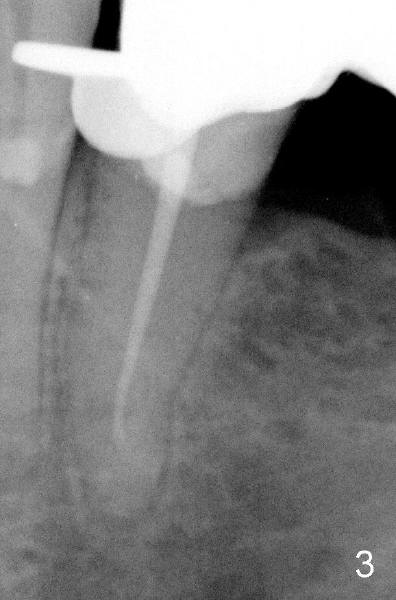

七十岁童太太因左下第二前磨牙(基牙)游走性牙痛就诊,有明显扣痛,第一前磨牙扣痛稍轻,仔细检查发现第二前磨牙颈部缺损,穿髓。开髓证实牙髓坏死,根管口椭圆形,颊舌侧宽,怀疑有舌侧第二根管,但是最后后者好像融合于颊侧根管。图一是五年前拍摄的根尖片(P2:第二前磨牙),图二最近拍摄的:根管治疗前,但是没有拍摄第二张angled PA,图三术中:插入主牙胶尖40/.06,不到19.5毫米(离根尖2.45毫米),一般使用Apex locator决定working length,但是从PFM retainer开髓,Apex locator非常敏感,插入塑料小管也不好用,只好凭手感决定working length。当术中根尖片拍摄后,努力增加一些working length,但是没有特意弯曲细的根管扩大针,图四显示根管治疗完毕,working length19.5毫米,使用cold condensation,离根尖1.58毫米,用树脂封闭根管治疗开口。

根据术前PA图1,2和术后PA图3,4比较,RCT的P2有术后的wide apical PDL,提示有根尖炎症。另外,P2的根管Cleaning,Shaping和充填没有至根尖孔,会增加P2 RCT 失败的可能性。从4张PA中,我没有看到有另外的根管存在,至少在apex 以上的牙体没有发现,但你仍可多拍几张前后45度的X-ray看看,牙体的CT不是Standard of Care, 业界需时才能普遍接受,且另外收费,病人会拒绝,但如可能scan一下 It doesn't hurt.